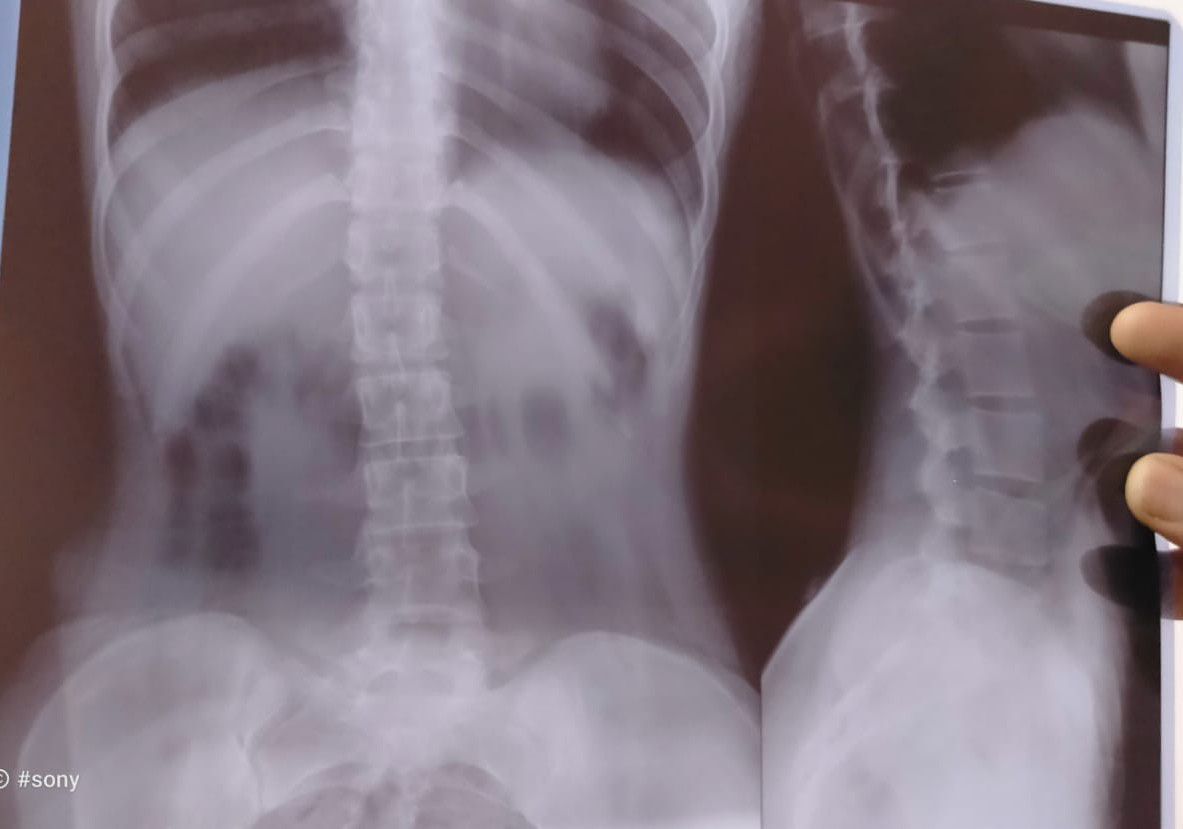

Please give your Valuable opinion

Pain

Hip

Numbness

Lowerlimbs

Radiating